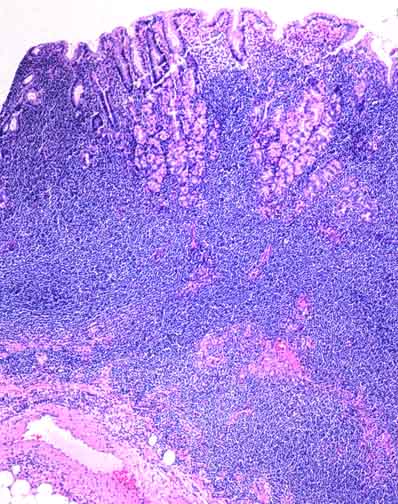

A low power view of a gastric maltoma. A clue to the malignant nature of this lymphoid infiltrate is its density and extent.

Focally the glands are invaded and destroyed by the lymphoid cells to produce a lymphoepithelial lesion, as seen here in the center. These lesions are particularly common in gastric maltomas.